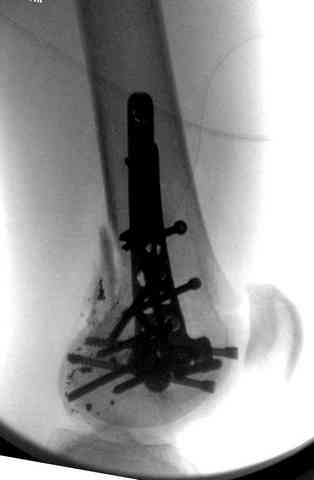

Здесь представлены несколько случаев лечения огнестрельного перелома

2 внутрисуставной перелом дистального бедра с удалением пули

3 сегментарный перелом бедра с переломом Хоффа фрагментом, сделано из минимального доступа